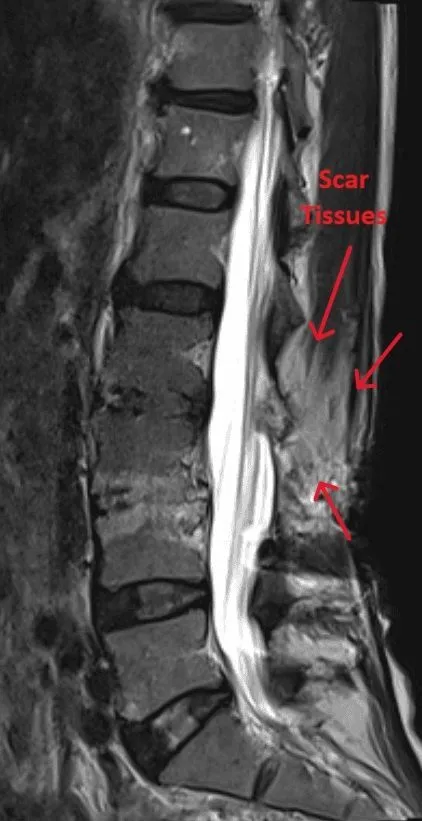

MRI scan of a spine showing scar tissues marked with red arrows.

Excessive Scar Tissue

Dense scar tissue forms around the implant and nerves, causing chronic pain and compression.